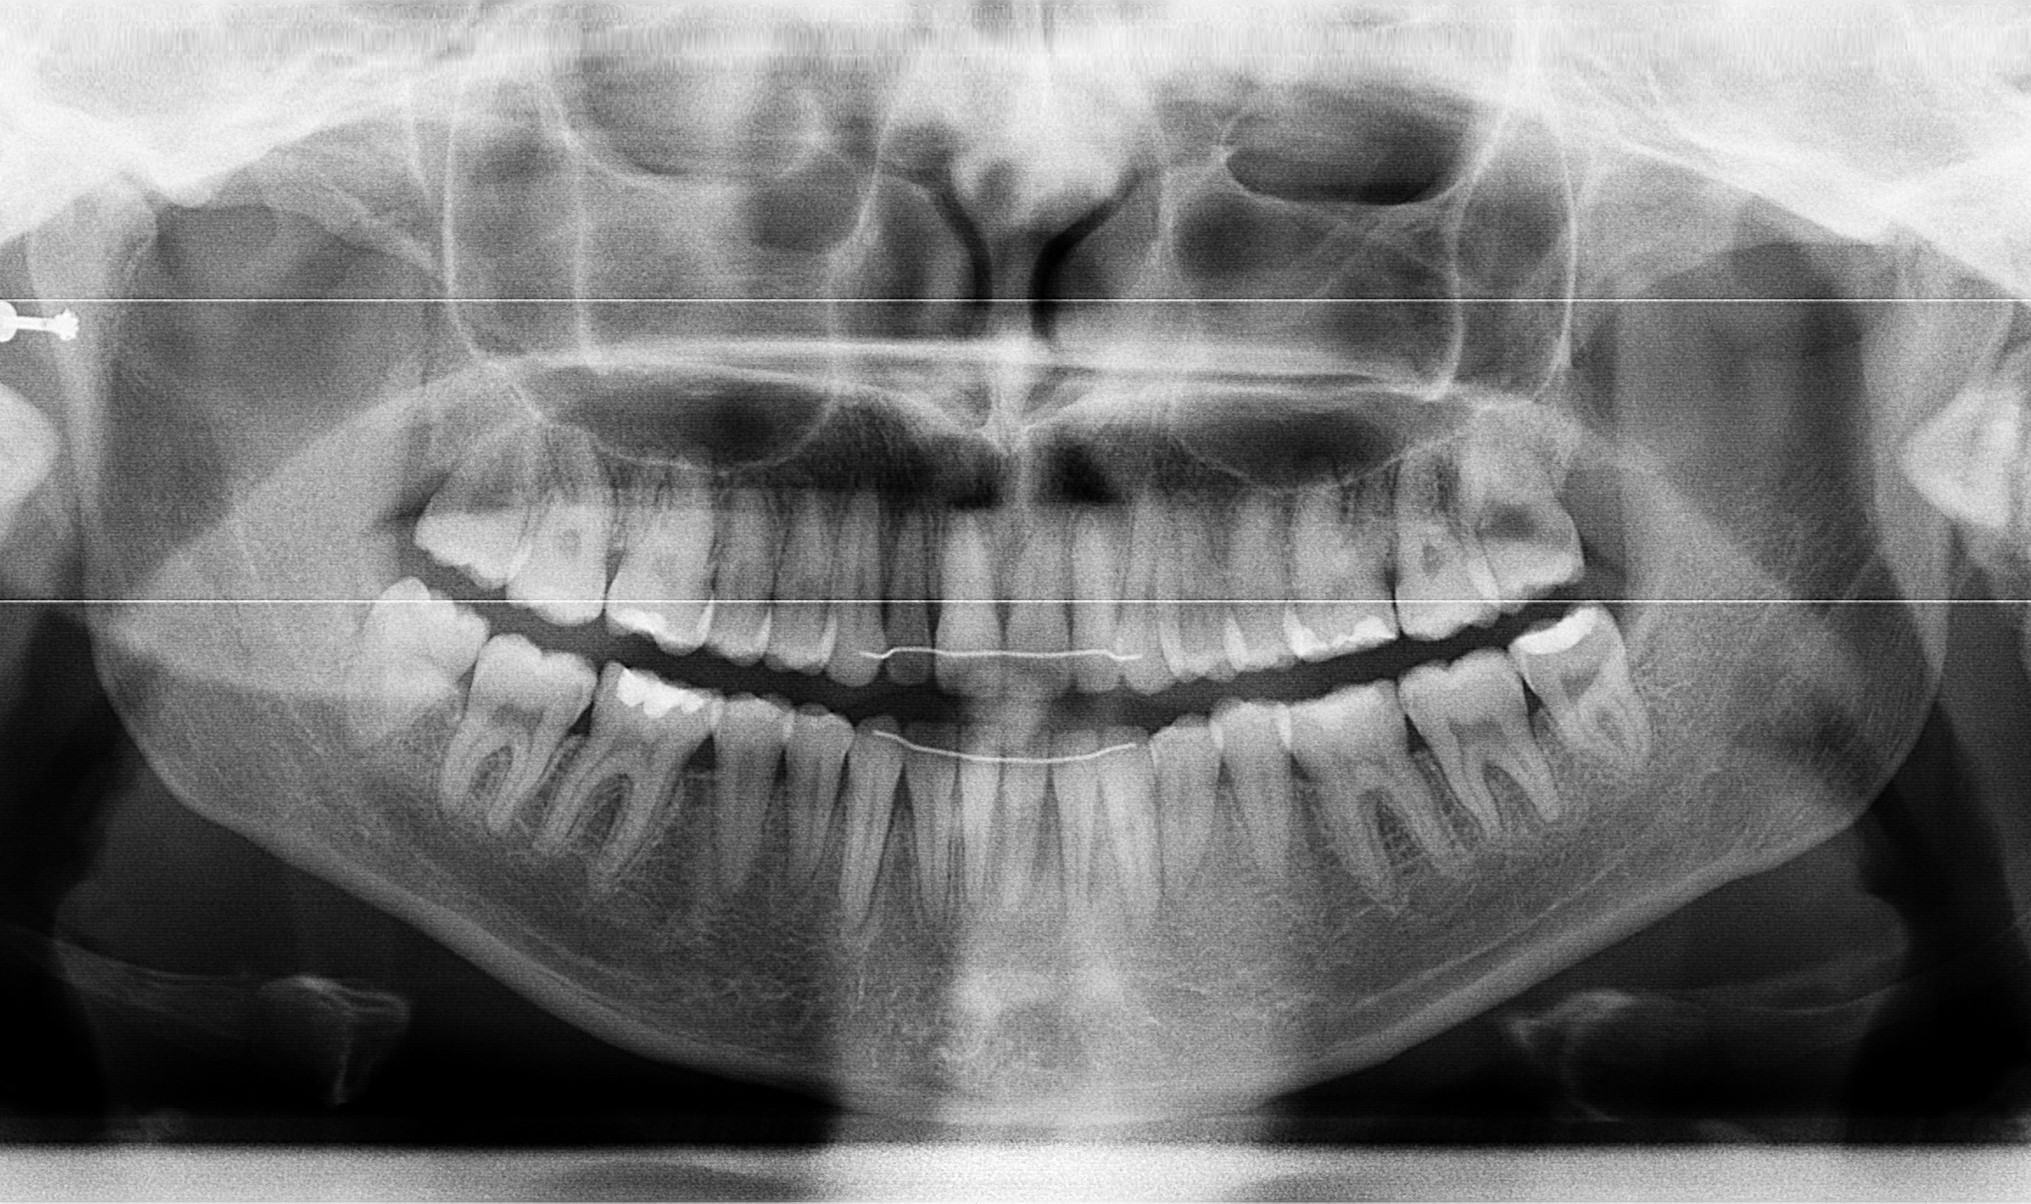

A 22-year-old female patient presented with a Class III malocclusion. She does not like her own profile. Her facial profile was straight with a slightly retrusive maxilla, the upper incisors were within normal inclination, and the lower incisors were retroclined. Bolton discrepency is on mandible for 6 teeth. A retruded upper lip and a normally positioned lower lip were noted. There was also a marked lack of midface support, and the constricted dental arches resulted in a narrow smile and pronounced dark buccal corridors.

Initial leveling in the maxillary arch was carried out with a 0.014 CuNiTi archwire. This was followed by a 0.018 CuNiTi wire, with stoppers positioned mesial to the molars and activated to provide protrusion of incisors. The mandibular arch was then bonded and initial alignment was achieved with a 0.014 CuNiTi wire, then both jaws are progressing to 0.014 × 0.0275 CuNiTi and subsequently 0.018 × 0.0275 CuNiTi for torque control.

Finishing was completed with a 0.018 × 0.0275 TMA archwire in conjunction with Class III elastics.

At the end of treatment, the patient’s occlusion was corrected to Class I molar and canine relationships with a physiological overjet and overbite. Irregularities in both arches were eliminated, arch forms were coordinated, and incisor torque was effectively controlled to position the roots centrally within the alveolar bone, enhancing stability. Satisfactory intercuspation was achieved in both the anterior and posterior segments, with maintenance of midline coincidence and periodontal health throughout treatment. The case was finished and transitioned into the retention phase using fixed retainers in the maxillary and mandibular anterior regions.